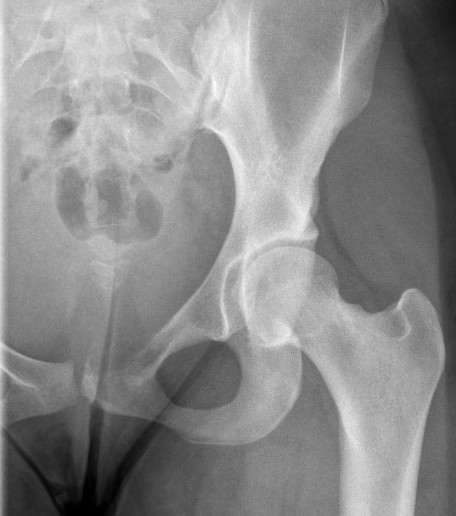

Ewings superior pubic rami